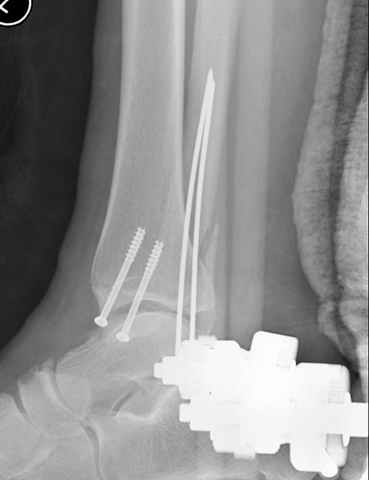

Второй случай сделан из одного разреза

Дж

ЕЧ LISS plate, mininvasive approach - luxurous !

На прямой проекции послеоперационного Рг макроскопически все выглядит очень анатомично, при микроскопическом ( :-)) ) рассмотрении можно все-таки заметить вальгизацию тарана, суставная щель в латеральном отделе сустава несколько уже , чем в медиальном при отсутствии латерального смещения тарана. У меня был аналогичный случай (без LISS , без мини доступа) с вальгусным наклоном тарана при восстановленном ankle mortise при последовательном наблюдении с интервалами в 6-8 недель в послеоперационном периоде отмечалось прогрессирующее сужение суставной щели в латеральном отделе сустава, закончившееся посттравматическим ОА, к счастью боли умеренные, купируемые аналгетиками или своими эндорфинами:-))(активная пациентка, у которой нет времени на болезни....) Какова жизненная ситуация в приведенном вами случае? И последнее, что я хотел бы прояснить для себя - фиксация внутренней лодыжки: я обычно комбинирую фиксацию компрессирующим винтом со спицей - по идее ротационная стабильность должна быть лучше, чем один винт, каковы ваши наблюдения в этом плане?